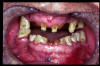

CM Enfermedad periodontal avanzada con caries. Mala higiene.